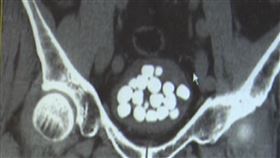

翁肚子痛 醫驚:體內一窩「鵪鶉蛋」

中國一名68歲的丁姓阿伯有頻尿的問題,約半小時就要上...